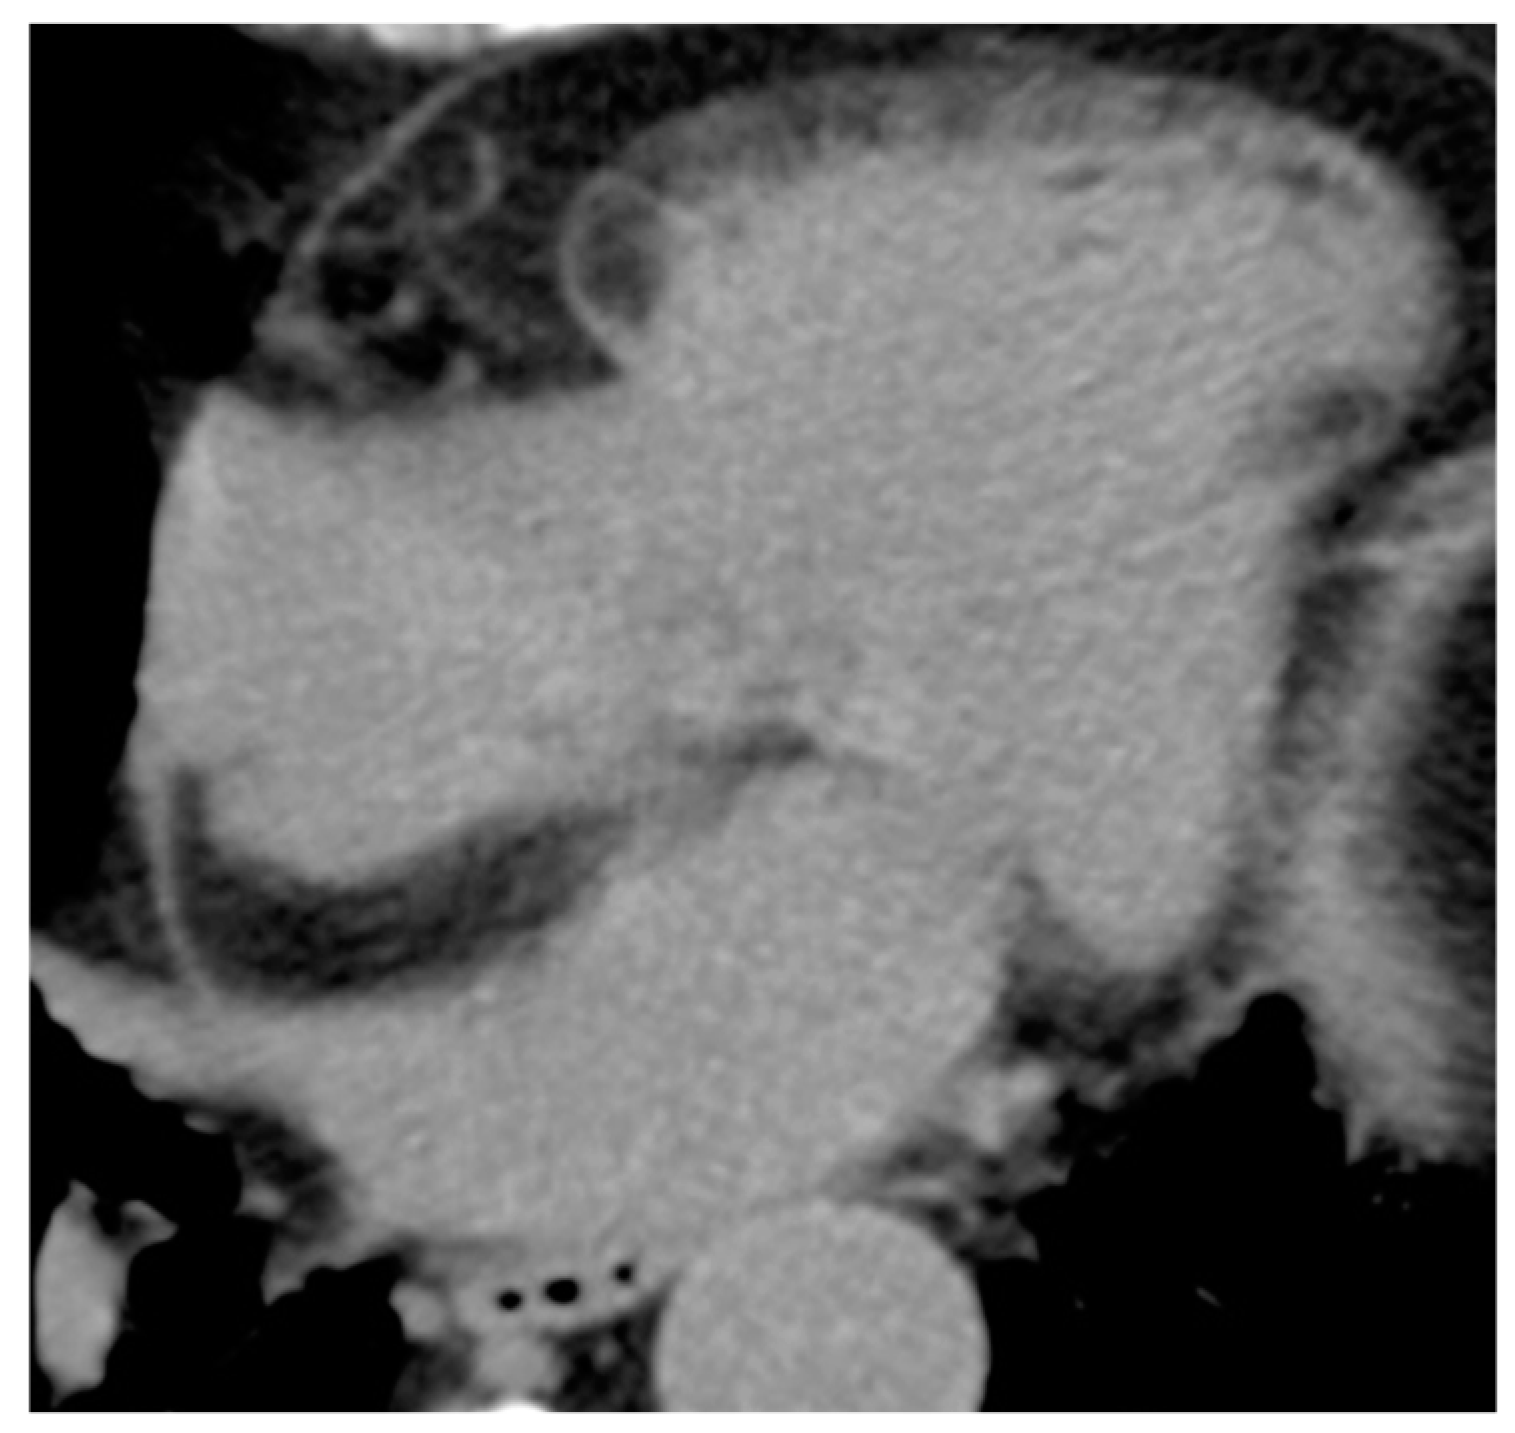

4.1. Myxoma

| Myxoma | Adulthood. Carney complex. | LA | Usually, asymptomatic. Rarely, intracardiac obstruction, embolic events and constitutional symptoms | Mobile mass arising from the IAS | Globular or spherical, with a friable surface and heterogeneous internal echogenicity | Heterogeneous, low attenuation, may be calcified | Isointense T1w, High T2w, heterogeneous LGE |